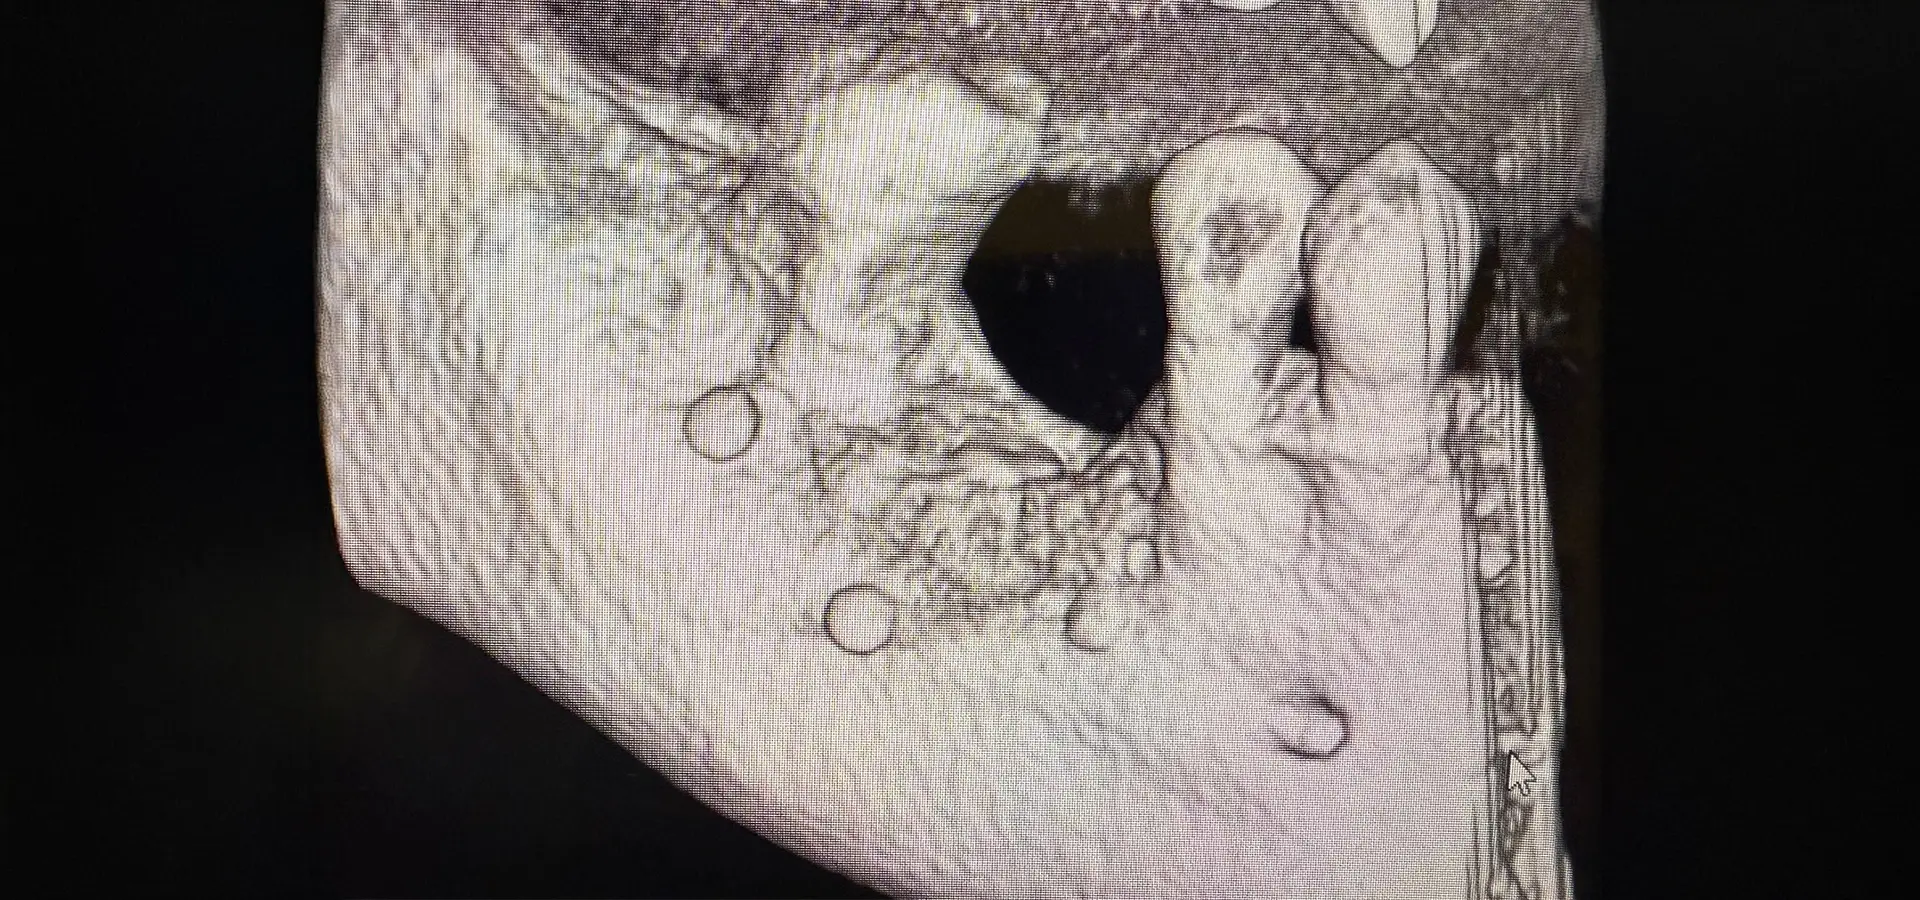

Solo una TAC Cone Beam 3D permette di valutare con precisione millimetrica l’entità della perdita ossea e di pianificare l’intervento rigenerativo più adatto.

Diagnosi Digitale 3D: La Base per una Rigenerazione Ossea Predicibile

Una rigenerazione ossea efficace e sicura nasce sempre da una diagnosi digitale accurata. La TAC Cone Beam 3D rappresenta oggi lo standard diagnostico per la valutazione pre-implantare, permettendo di visualizzare con precisione millimetrica l’anatomia ossea tridimensionale, la posizione di strutture nobili (nervo alveolare inferiore, seno mascellare, forame mentoniero) e la densità ossea.

L’integrazione tra imaging 3D e scanner intraorale digitale consente di creare un progetto chirurgico virtuale completo: attraverso software di pianificazione implantare, è possibile simulare la ricostruzione ossea, definire il volume di biomateriale necessario, posizionare virtualmente gli impianti nella posizione ideale (sia dal punto di vista protesico che chirurgico) e calcolare i tempi di guarigione previsti in base alla complessità del caso.

Questo approccio digitale offre vantaggi concreti: riduce il margine di errore chirurgico, permette di prevedere eventuali difficoltà operative, consente di comunicare al paziente in modo chiaro e visivo il piano di trattamento e, nei casi complessi, permette di realizzare guide chirurgiche personalizzate che trasferiscono la pianificazione virtuale direttamente in bocca durante l’intervento, garantendo precisione millimetrica.